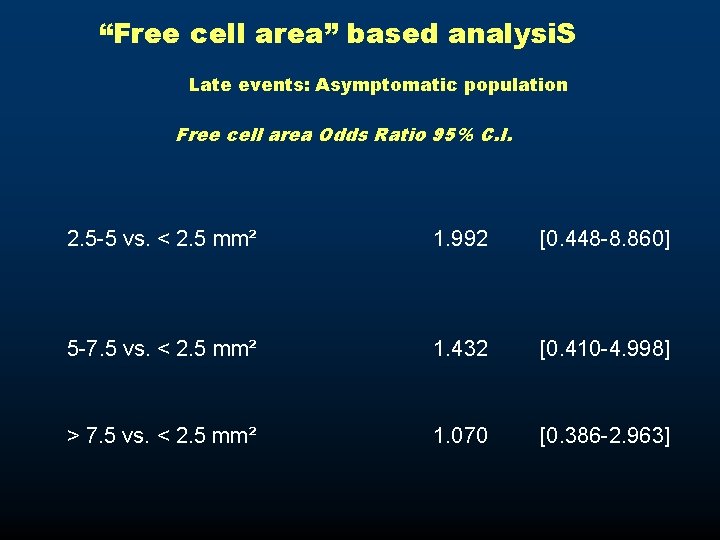

“Free cell area” based analysi. S Late events: Asymptomatic population Free cell area Odds Ratio 95% C. I. 2. 5 -5 vs. < 2. 5 mm² 1. 992 [0. 448 -8. 860] 5 -7. 5 vs. < 2. 5 mm² 1. 432 [0. 410 -4. 998] > 7. 5 vs. < 2. 5 mm² 1. 070 [0. 386 -2. 963]